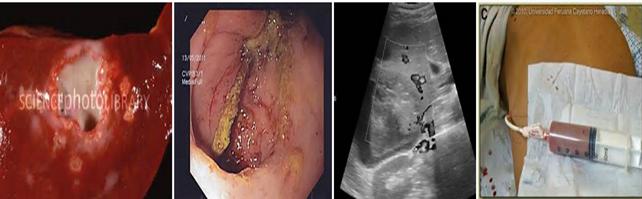

Nội soi đại trực tràng

-Soi trực tràng gây không nên tiến hành thường quy ở tất cả bệnh nhân vì có thể gây stress đau, chỉ cần thiết khi xét nghiệm phân âm tính và xuất huyết tiêu hóa và nghi ngờ ung thư đại trực tràng. Thủ thuật nội soi cho thấy niêm mạc trực tràng bị viêm rải rác, có những đốm loét hình miệng núi lửa, bao phủ một lớp nhày có chứa amíp ăn hồng cầu;

-Trong viêm loét đại tràng do amip, nhìn thấy niêm mạc phù nề, sưng đỏ, có sang thương loét nông hoặc sâu, nơi đấy có nhiều amíp.

Bệnh amíp ở gan là một biến chứng thường xảy ra sau bệnh amíp đường ruột cấp tính, đang tiến triển hay bệnh đã mắc từ lâu nhưng bệnh nhân không quan tâm. Xuất phát từ các sang thương ở đại tràng, thể hoạt động dưới dạng hoạt động ăn hồng cầu theo đường tĩnh mạch cửa vào gan. Mỗi amíp sẽ tăng sinh tạo thành một vết loét, nhiều vết loét kết hợp vào nhau tạo thành áp xe lớn. Trong áp xe có mủ màu sôcôla do máu trộn với mật trong hệ thống đường mật.

-Trước đây, khi một chẩn đoán nghi ngờ áp xe gan do amip thì thủ thuật chọc dò gan vừa thăm dò, vừa chẩn đoán rất phổ biến và như một bước thường quy. Chọc dò là một xét nghiệm xâm lấn, gây đau và nguy hiểm vì amíp có thể theo kim chọc dò lây sang các mô khác của cơ thể;

-Nếu đúng là áp xe gan do amíp sẽ hút ra mủ màu sôcôla, thường rất khó tìm sự hiện diện amíp trong mủ vì dạng hoạt động ký sinh ở vách áp xe chứ không ở trong mủ;